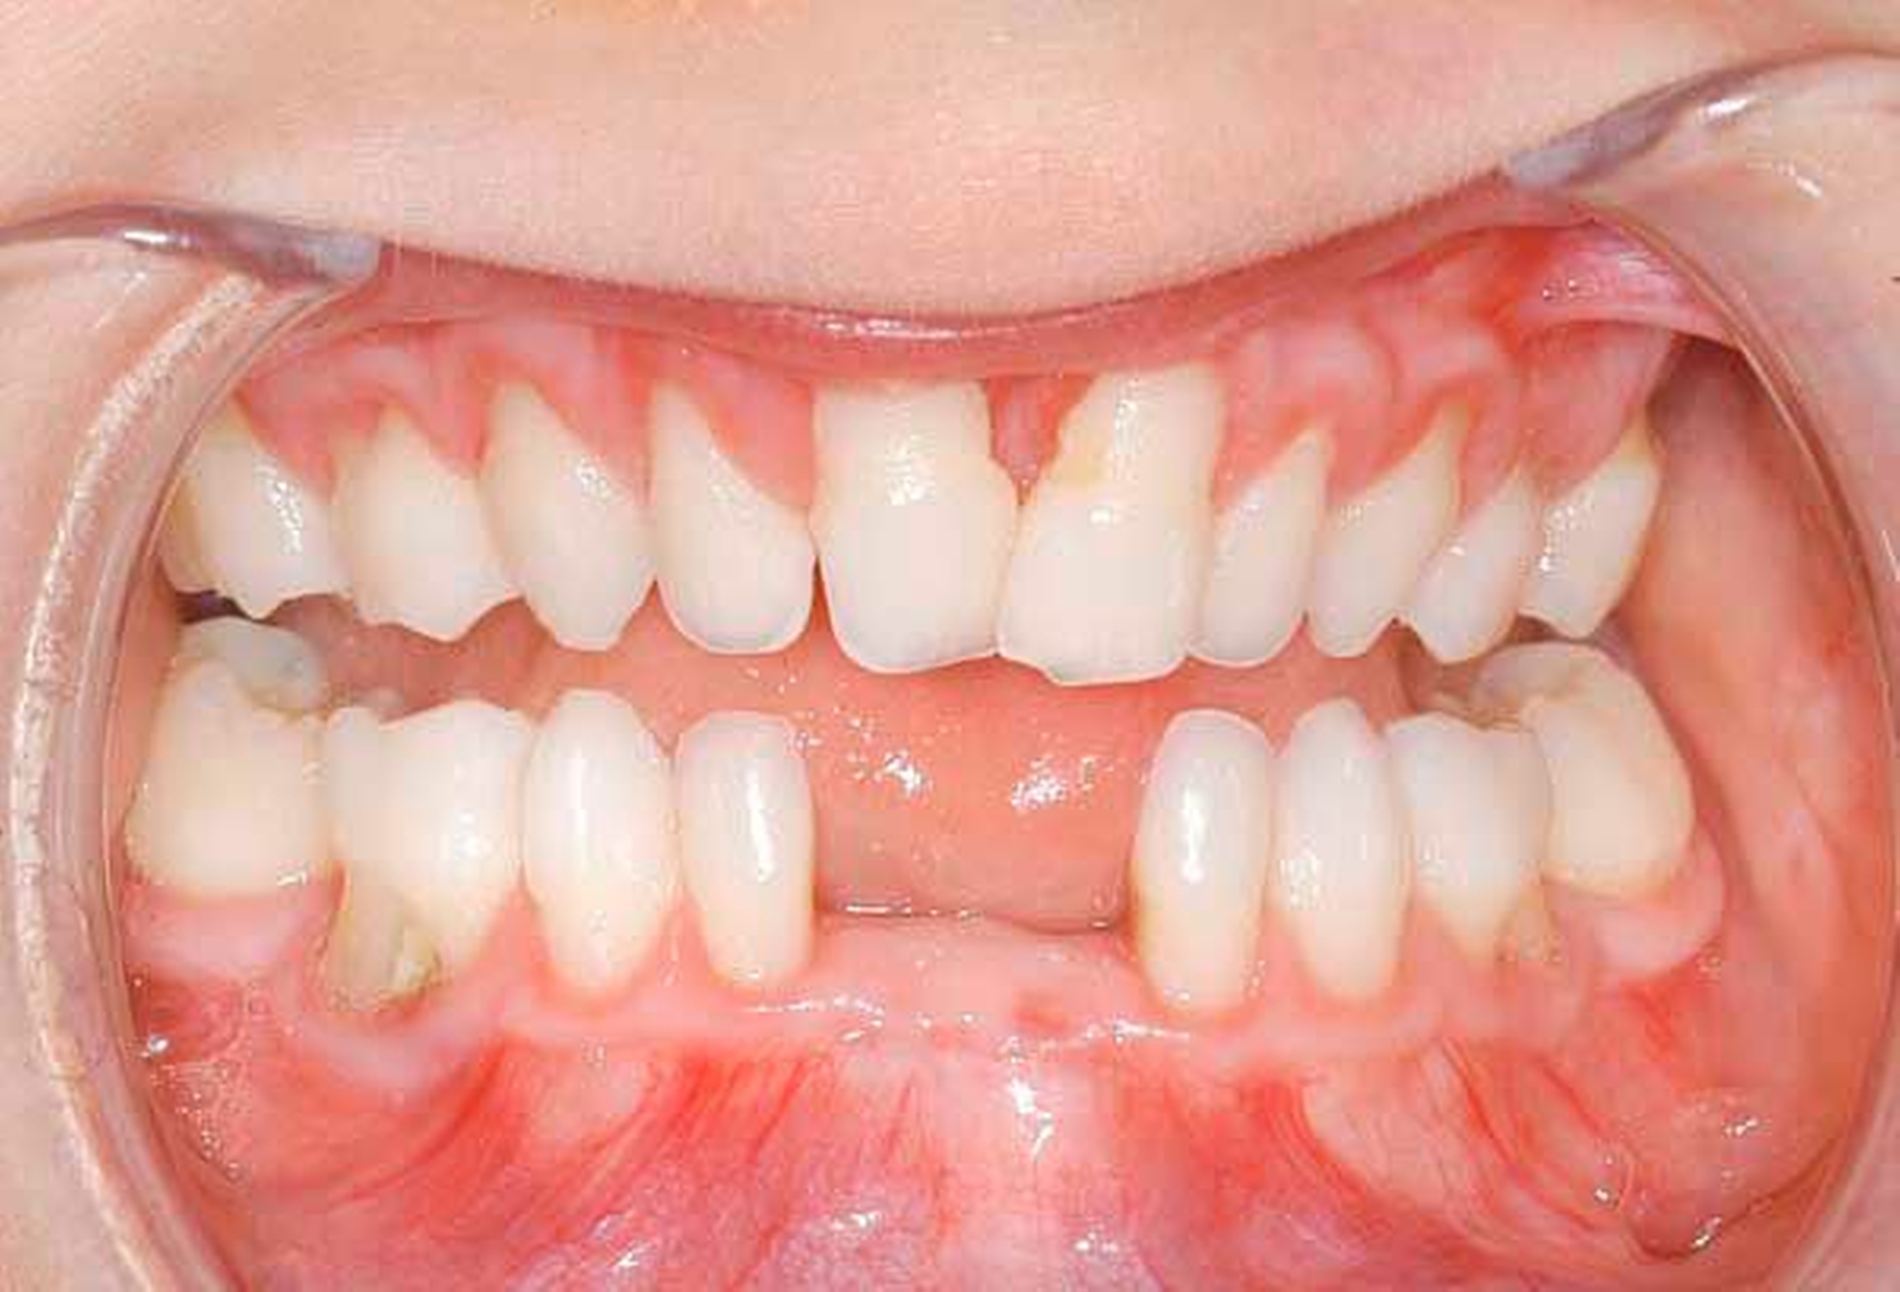

Eine 20-jährige Frau wird mit multiplen Nichtanlagen (Oligodontie) vorstellig. Sie berichtet, dass ihre Milchzähne vollständig angelegt waren. Mit dem einsetzenden Zahnwechsel habe sich jedoch herausgestellt, dass bei ihr multiple bleibende Zähne nicht angelegt waren. Insbesondere in der Pubertät habe sie sehr darunter gelitten, da sie wegen ihrer Zähne von den Mitschülern missachtet worden sei. Von verschiedenen Zahnärzten sei sie zwar auf die Möglichkeit einer Implantatversorgung hingewiesen worden, diese könne sie sich allerdings nicht leisten. Bei der intraoralen Inspektion zeigen sich ein seitlicher offener Biss, Formanomalien der mittleren Oberkiefer-Schneidezähne sowie multiple verbliebene Milchzähne. Der radiologische Befund bestätigt den Verdacht auf eine Oligodontie. Auf Nachfrage berichtet die Patientin, dass sie „wenig schwitze“.

Aufgrund der Befunde wird der Patientin eine genetische Beratung bei Verdacht auf eine WNT10A-Mutation vorgeschlagen. Die genetische Untersuchung bestätigt letztlich den Verdacht einer ektodermalen Dysplasie.

Oligodontie im Zusammenhang mit einer ektodermalen Dysplasie.